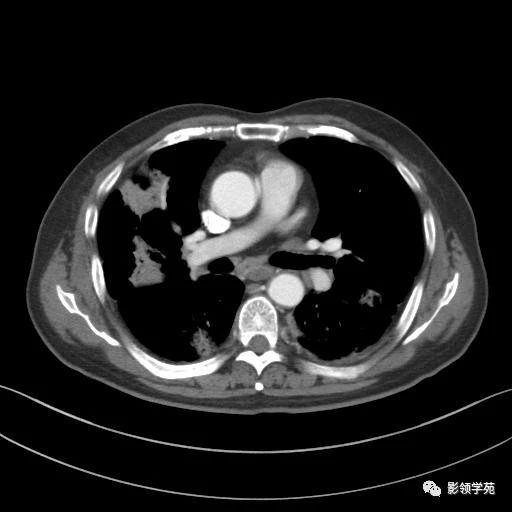

病例介绍

男,56岁,主因间断咳嗽,咳痰,发热伴关节疼痛3月就诊。

病理结果

灰白色穿刺组织2条,大者为1.2x0.05x0.05 cm,小者为0.9x0.05x0.05 cm,质软。(右肺)病变符合机化性肺炎。PAS染色(-)。

诊断

机化性肺炎;

双肺多发斑片影,考虑感染性病变可能。